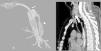

Iatrogenic tracheal rupture (ITR) is a serious complication secondary to procedures such as emergent orotracheal intubation or tracheostomy, among others. The management of ITR depends on the size, extension and location of the injury, along with the patient's respiratory status and comorbidities. The priority of treatment is to keep the airway permeable to ensure adequate ventilation. We present the case of a tracheal rupture after performing a percutaneous tracheostomy, in a patient diagnosed with severe acute respiratory distress syndrome secondary to bilateral interstitial pneumonia due to SARS-Cov-2. The issues are discussed, such as the management (conservative vs. surgical) depending on the features of the injury and the patient, in the extraordinary context that the COVID-19 pandemic has entailed.